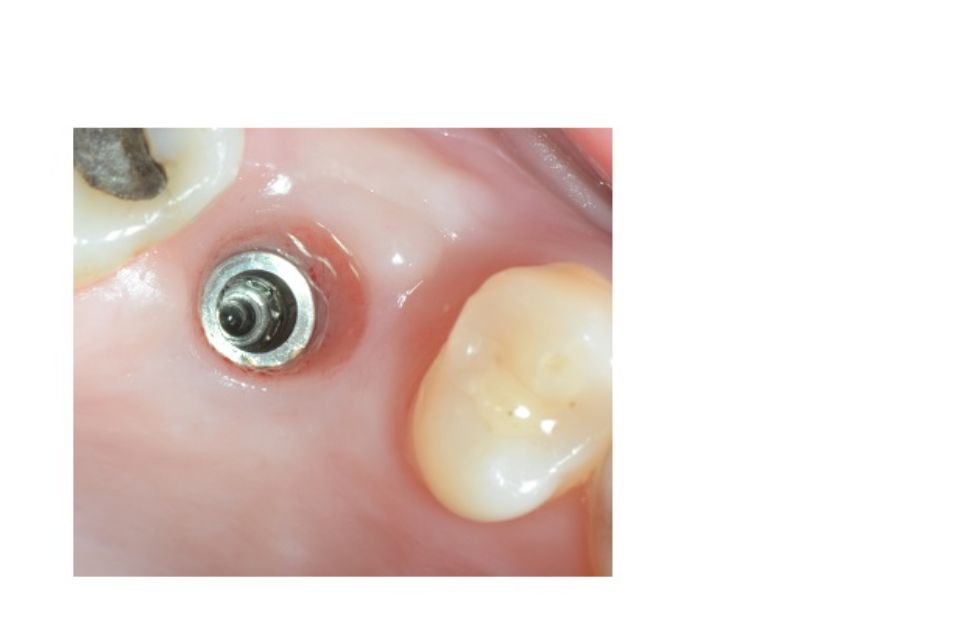

Implantología bucal

La implantología es la especialidad odontológica que se ocupa de la sustitución de la raíz del diente perdido.

La sustitución se hace mediante una pequeña intervención quirúrgica para colocar una pieza de titanio dentro del hueso maxilar.

El implante tiene una rosca en su interior donde posteriormente se enroscará el pilar que soportará la corona protética.